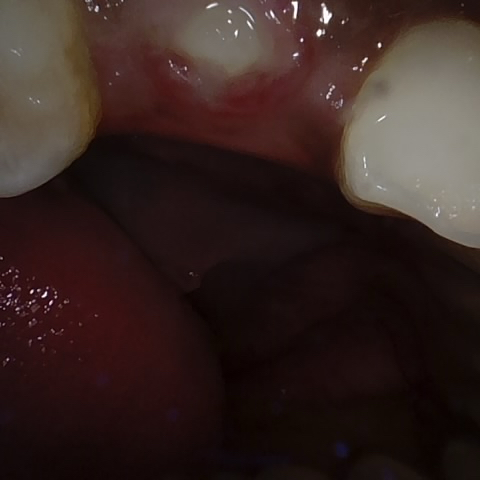

Annotated as "Good"